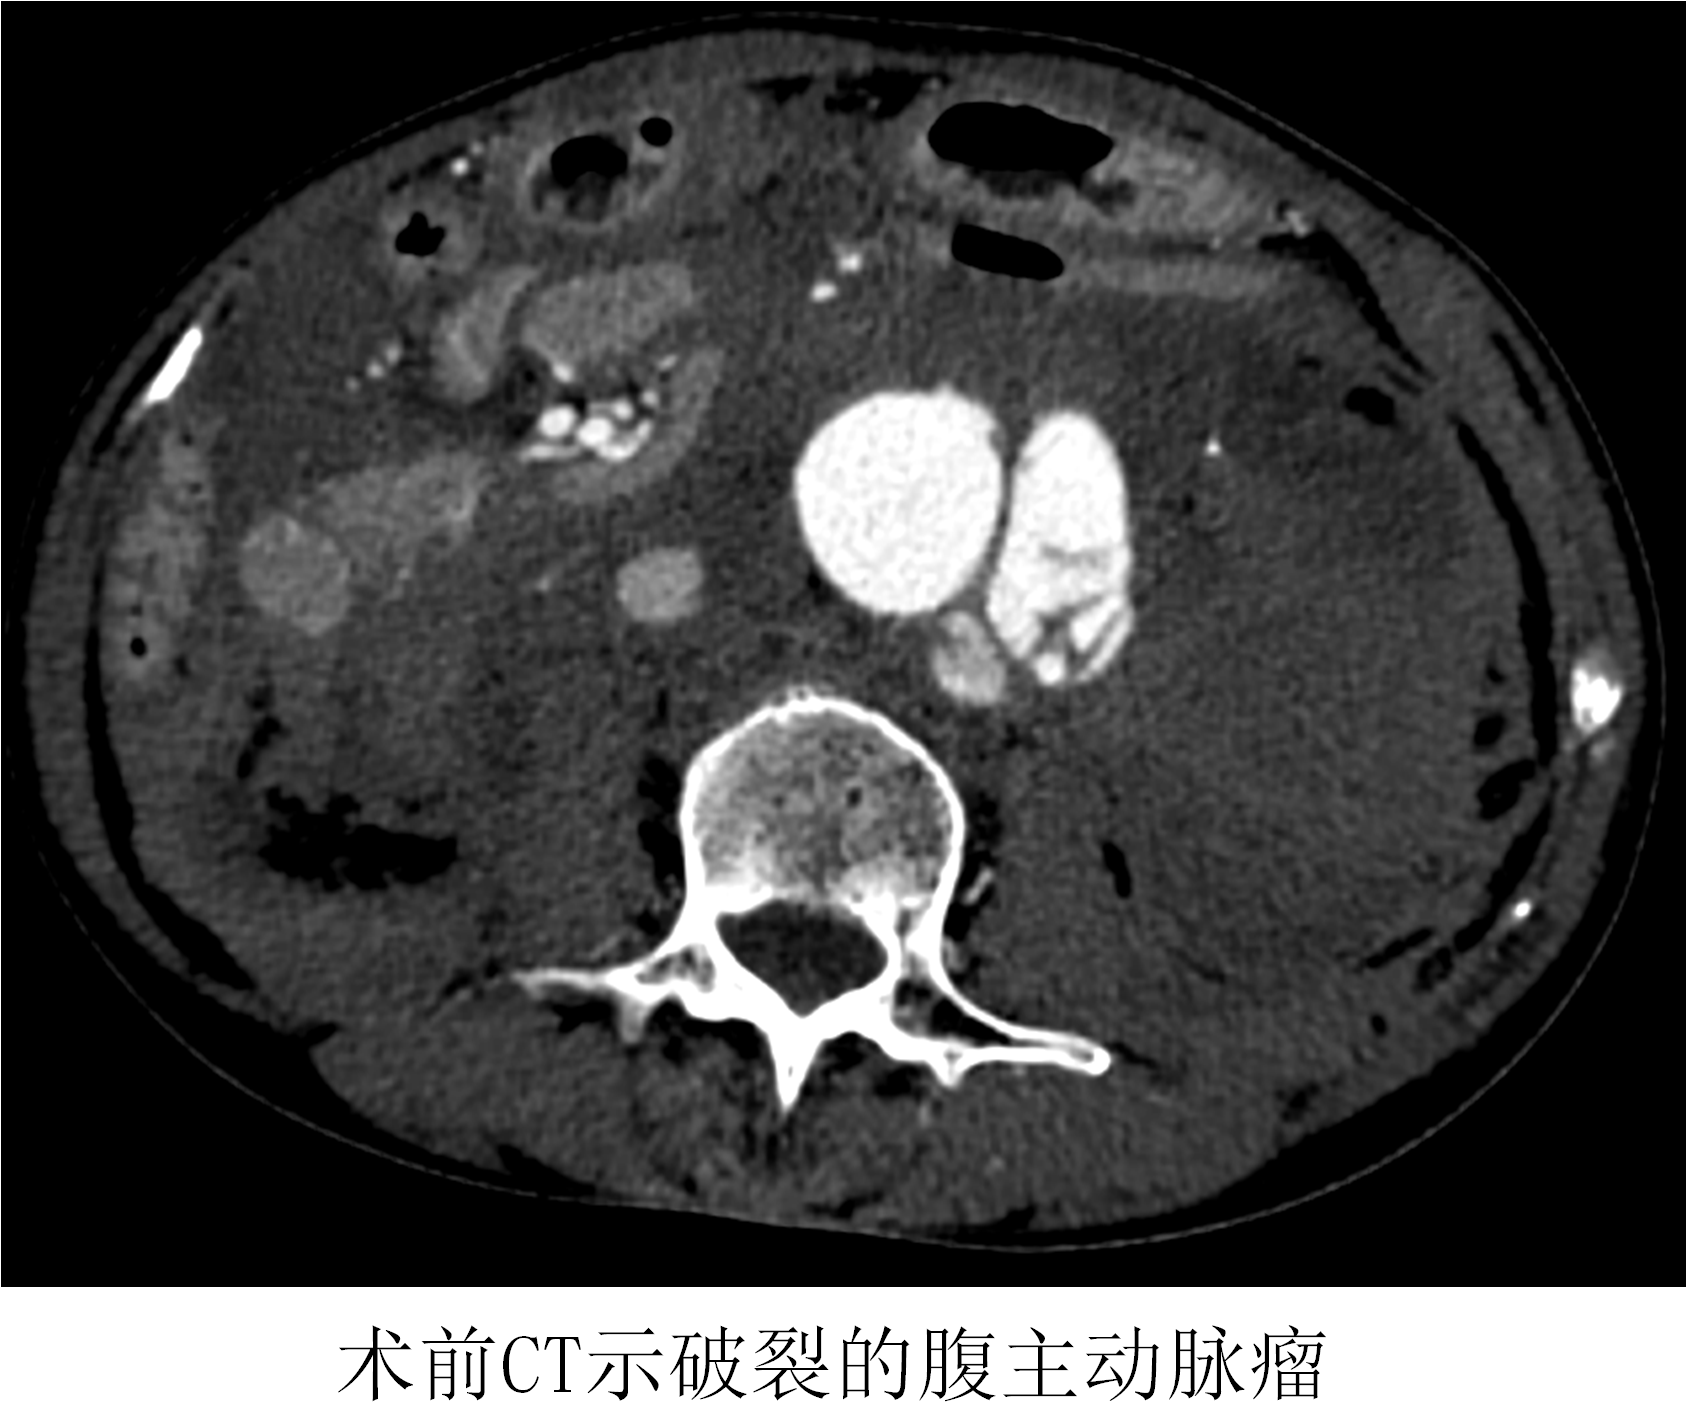

薛冠華在得知患者情況后,立刻從家中趕往醫(yī)院,開(kāi)始了這場(chǎng)與死神的賽跑;颊咴诩痹\抗休克治療的同時(shí),半小時(shí)內(nèi)完成所有檢查,隨即被送入復(fù)合手術(shù)室。此時(shí)患者的血壓繼續(xù)下降,最低時(shí)只有60/30mmHg。

時(shí)間就是生命!在來(lái)不及全麻的情況下,薛冠華當(dāng)機(jī)立斷,局麻手術(shù)。手術(shù)由薛冠華主刀、倪其泓和王預(yù)立醫(yī)師共同協(xié)助,在麻醉醫(yī)師黃丹、手術(shù)室護(hù)士夏悅和放射科技師馬鋆的配合下緊張進(jìn)行。薛冠華通過(guò)精準(zhǔn)定位,在避免影響內(nèi)臟血管的同時(shí),采用腔內(nèi)技術(shù)在短短30分鐘內(nèi)就將腹主動(dòng)脈瘤的破口通過(guò)覆膜支架封堵,有效阻止了進(jìn)一步出血;颊叩难獕洪_(kāi)始回升,情況逐漸平穩(wěn),手術(shù)順利完成;颊咿D(zhuǎn)入重癥監(jiān)護(hù)室后意識(shí)慢慢恢復(fù),術(shù)后10天復(fù)查CT顯示破裂的腹主動(dòng)脈瘤隔絕良好,已于近期康復(fù)出院。